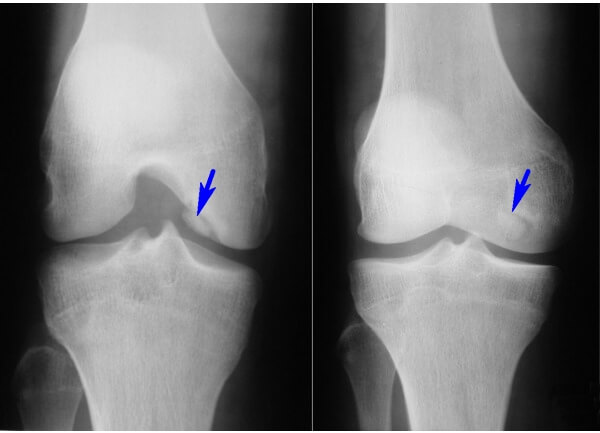

Чаще всего назначается рентгеноскопия. На рентгеновских снимках четко просматриваются некрозированные участки кости, а также обнаруживаются визуальные следы суставных мышей. Однако рентген не отражает состояния хрящевой ткани.

- На 1-й стадии процесс еще развивается медленно и проходит практически бессимптомно. На рентгене обнаруживаются участки некроза. Сам хрящ уже начинает размягчаться, что может выражаться незначительным выпячиванием в суставную полость.

- Для 2-й стадии характерно образование уплотнений, которые отделяются от поверхности. Это выглядит как вздутие. На рентгене четко определяется очаг поражения. К болевой симптоматике присоединяется воспаление, отечность сустава. Боль четко ощущается при пальпации и во время определенных движений ногой.

- На 3-й стадии отмерший хрящ и кость частично отрываются. Рентгенограмма показывает тень суставной мыши. Возможна блокада сустава.